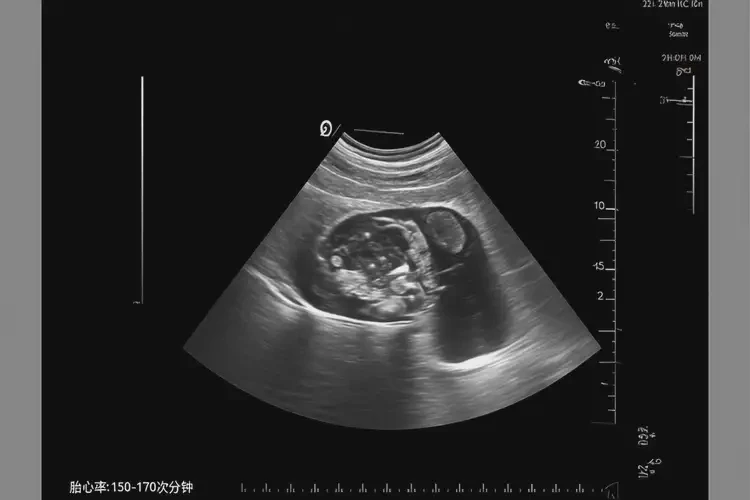

胎心率72次/分钟在怀孕2个月时可能存在风险。正常情况下,怀孕2个月的胎心率应在150-170次/分钟之间。胎心率低于120次/分钟可能表示胎儿心动过缓,需要进一步监测和评估。

• 怀孕早期(1-3个月):胎心率通常在150-170次/分钟之间。

怀孕2个月胎心率72有危险吗(图1)